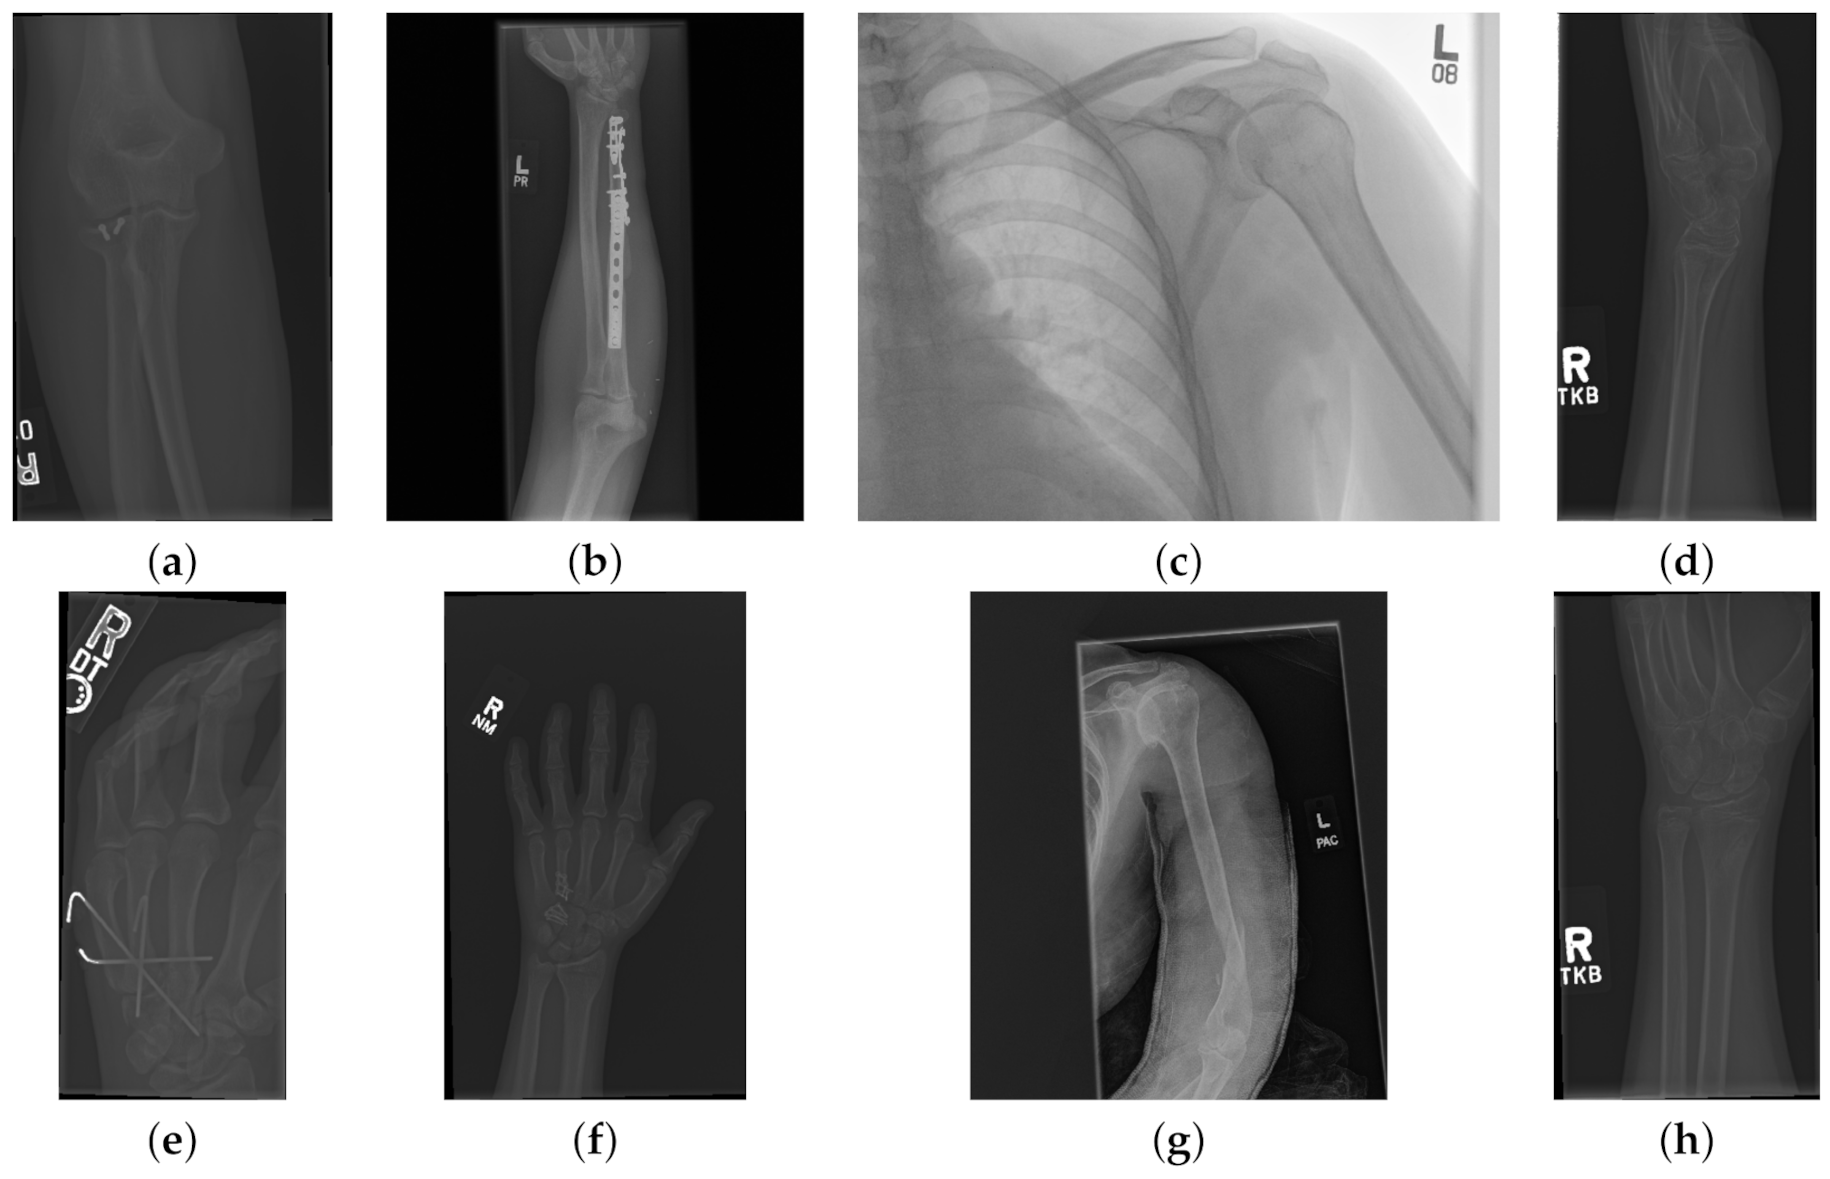

The data used to compare the 11 CNNs was obtained from the public dataset MUsculoskeletal RAdiographs (MURA) from a competition organised by researchers from Stanford University [59]. The dataset has been manually labelled by board-certified radiologists between 2001 and 2012. The studies (n = 14,656) are divided into training (n = 13,457), and validation (n = 1199). Furthermore, the studies have been allocated in groups called abnormal (i.e., those radiographs that contained fractured bones, foreign bodies such as implants, wires or screws, etc.) () or normal (). Representative normal cases are illustrated in Figure 1 and abnormal cases in Figure 2. The distribution per anatomical region is shown in Table 1. In this paper, the subset of the wrists was selected. The cases of normal and abnormal wrist radiographs is presented in Table 2. Notice that these were subdivided into four studies.

Figure 2.

Eight examples of radiographs with abnormalities (considered positive) of the Musculoskeletal Radiographs (MURA) dataset [59]. (a) Elbow, (b) Forearm, (c) Shoulder, (d) Wrist (lateral view), (d) Lateral view of Wrist, (e) Finger, (f) Hand, (g) Humerus, (h) Wrist. As for the cases without abnormalities, it should be noted the variability of the images and in addition the abnormalities themselves. There are cases of metallic implants some of which are smaller (a) than others (b), as well as fractures.